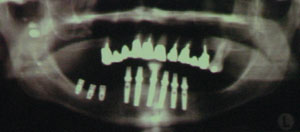

右の写真は下顎左側臼歯部にインプラントを希望されている患者のレントゲン写真です(写真では右側)。

右の写真は下顎左側臼歯部にインプラントを希望されている患者のレントゲン写真です(写真では右側)。IGIを用いた実際のケース

右の写真は下顎左側臼歯部にインプラントを希望されている患者のレントゲン写真です(写真では右側)。

右の写真は下顎左側臼歯部にインプラントを希望されている患者のレントゲン写真です(写真では右側)。

右側臼歯には短いインプラントが既に埋入されています。これは下のアゴの中に存在する神経の管を傷つけないようにするため、前医があえて短いインプラントを埋入したものです。しかしながら短いインプラントは、安定性に難があるのは否めません。

実際にインプラントを植立したレントゲン写真です。術後の神経麻痺もなく良好な結果となっています。

また上のインプラントの植立予定位置と寸分変わりなく、実際に埋められているのが分かります。(Case by Dr Y. Yeroshalmi, Israel)